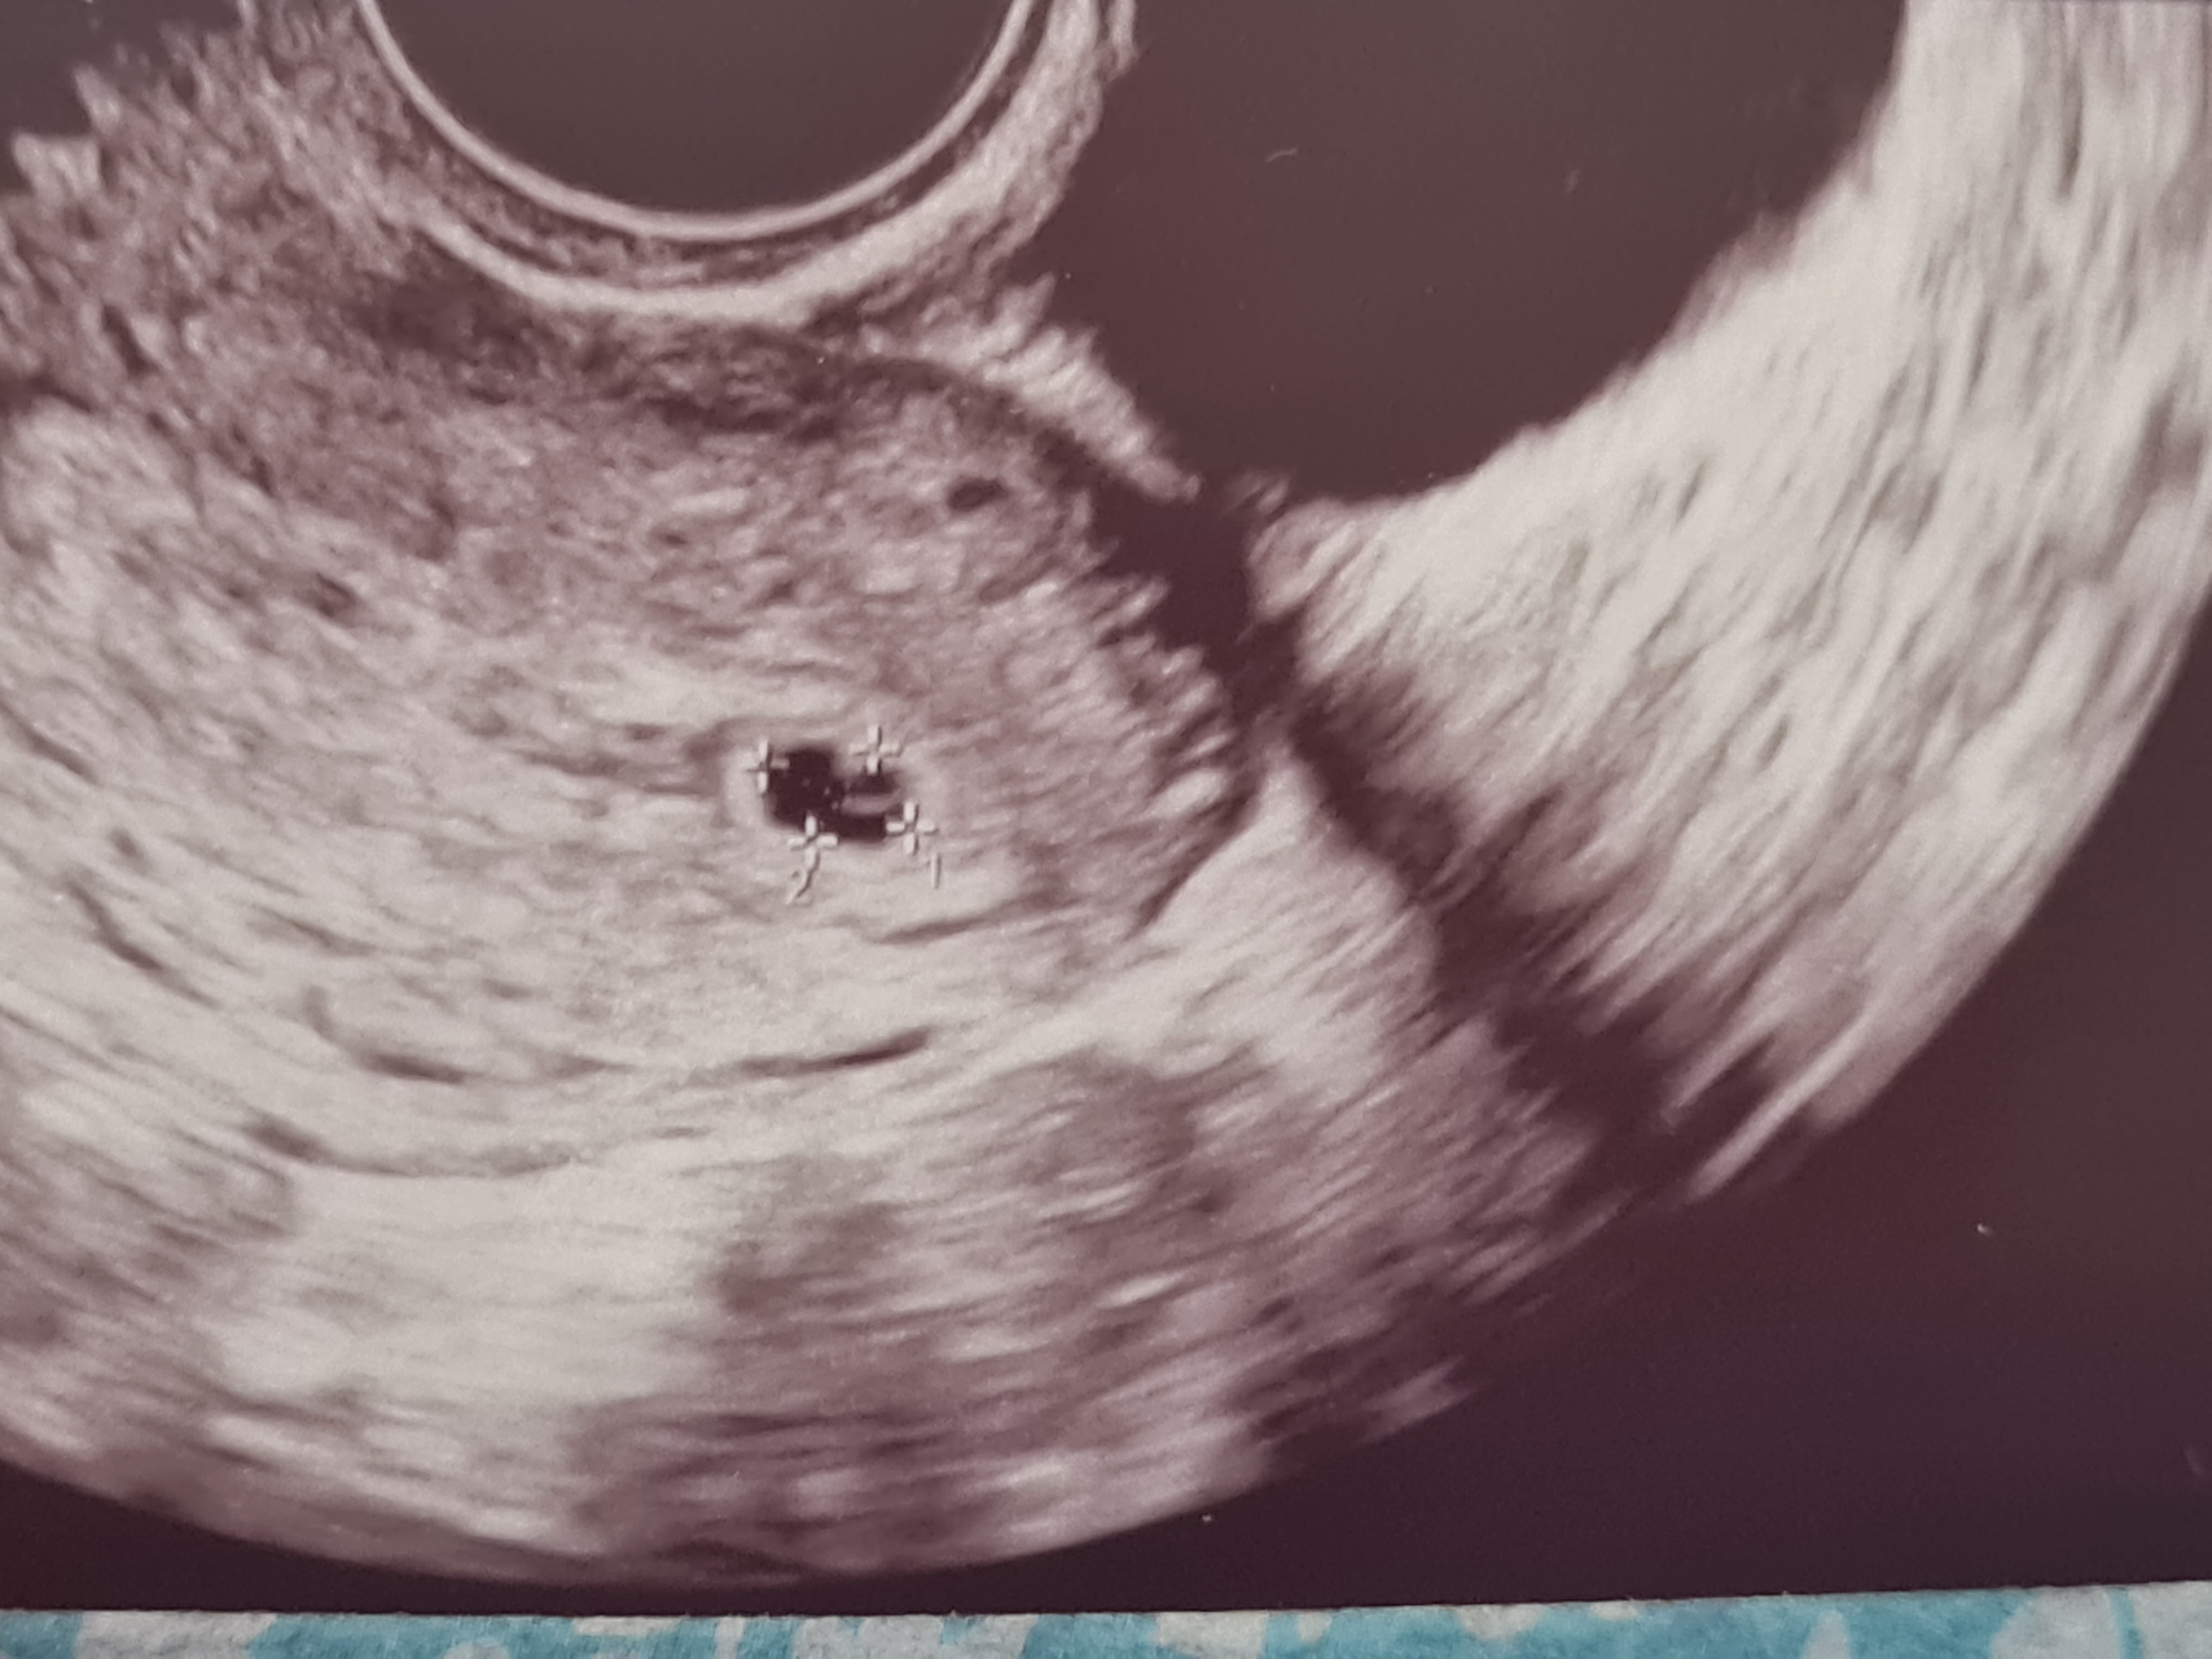

J'ai eu une écho hier j'étais à 5sa + 5 jours. On ne voit pas grand chose, je voulais savoir si c'était normal? Le gyneco me dit que oui mais moi ca me stress un petit peu. Je vous montre l'écho

Bienvenue à toi Flooche ! Ton écho parait tout à fait normale pour 5SA+5, à ce stade on ne voit que le sac et la vésicule vitelline, qui est très bien visible sur la tienne :) Je te mets la mienne pour ma précédente grossesse à 5SA+3 où tout était encore normal.

Bonjour Ninebay merci beaucoup pour ta réponse, en effet nous échos se ressemblent bcp ca me rassure énormément merci